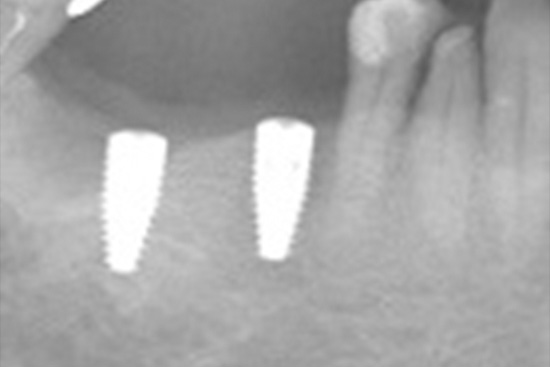

インプラント治療の症例

治療前

治療後

| 主訴 | 歯がない所が気になる |

|---|---|

| 治療期間 | 3ヶ月 |

| 治療内容 | インプラント |